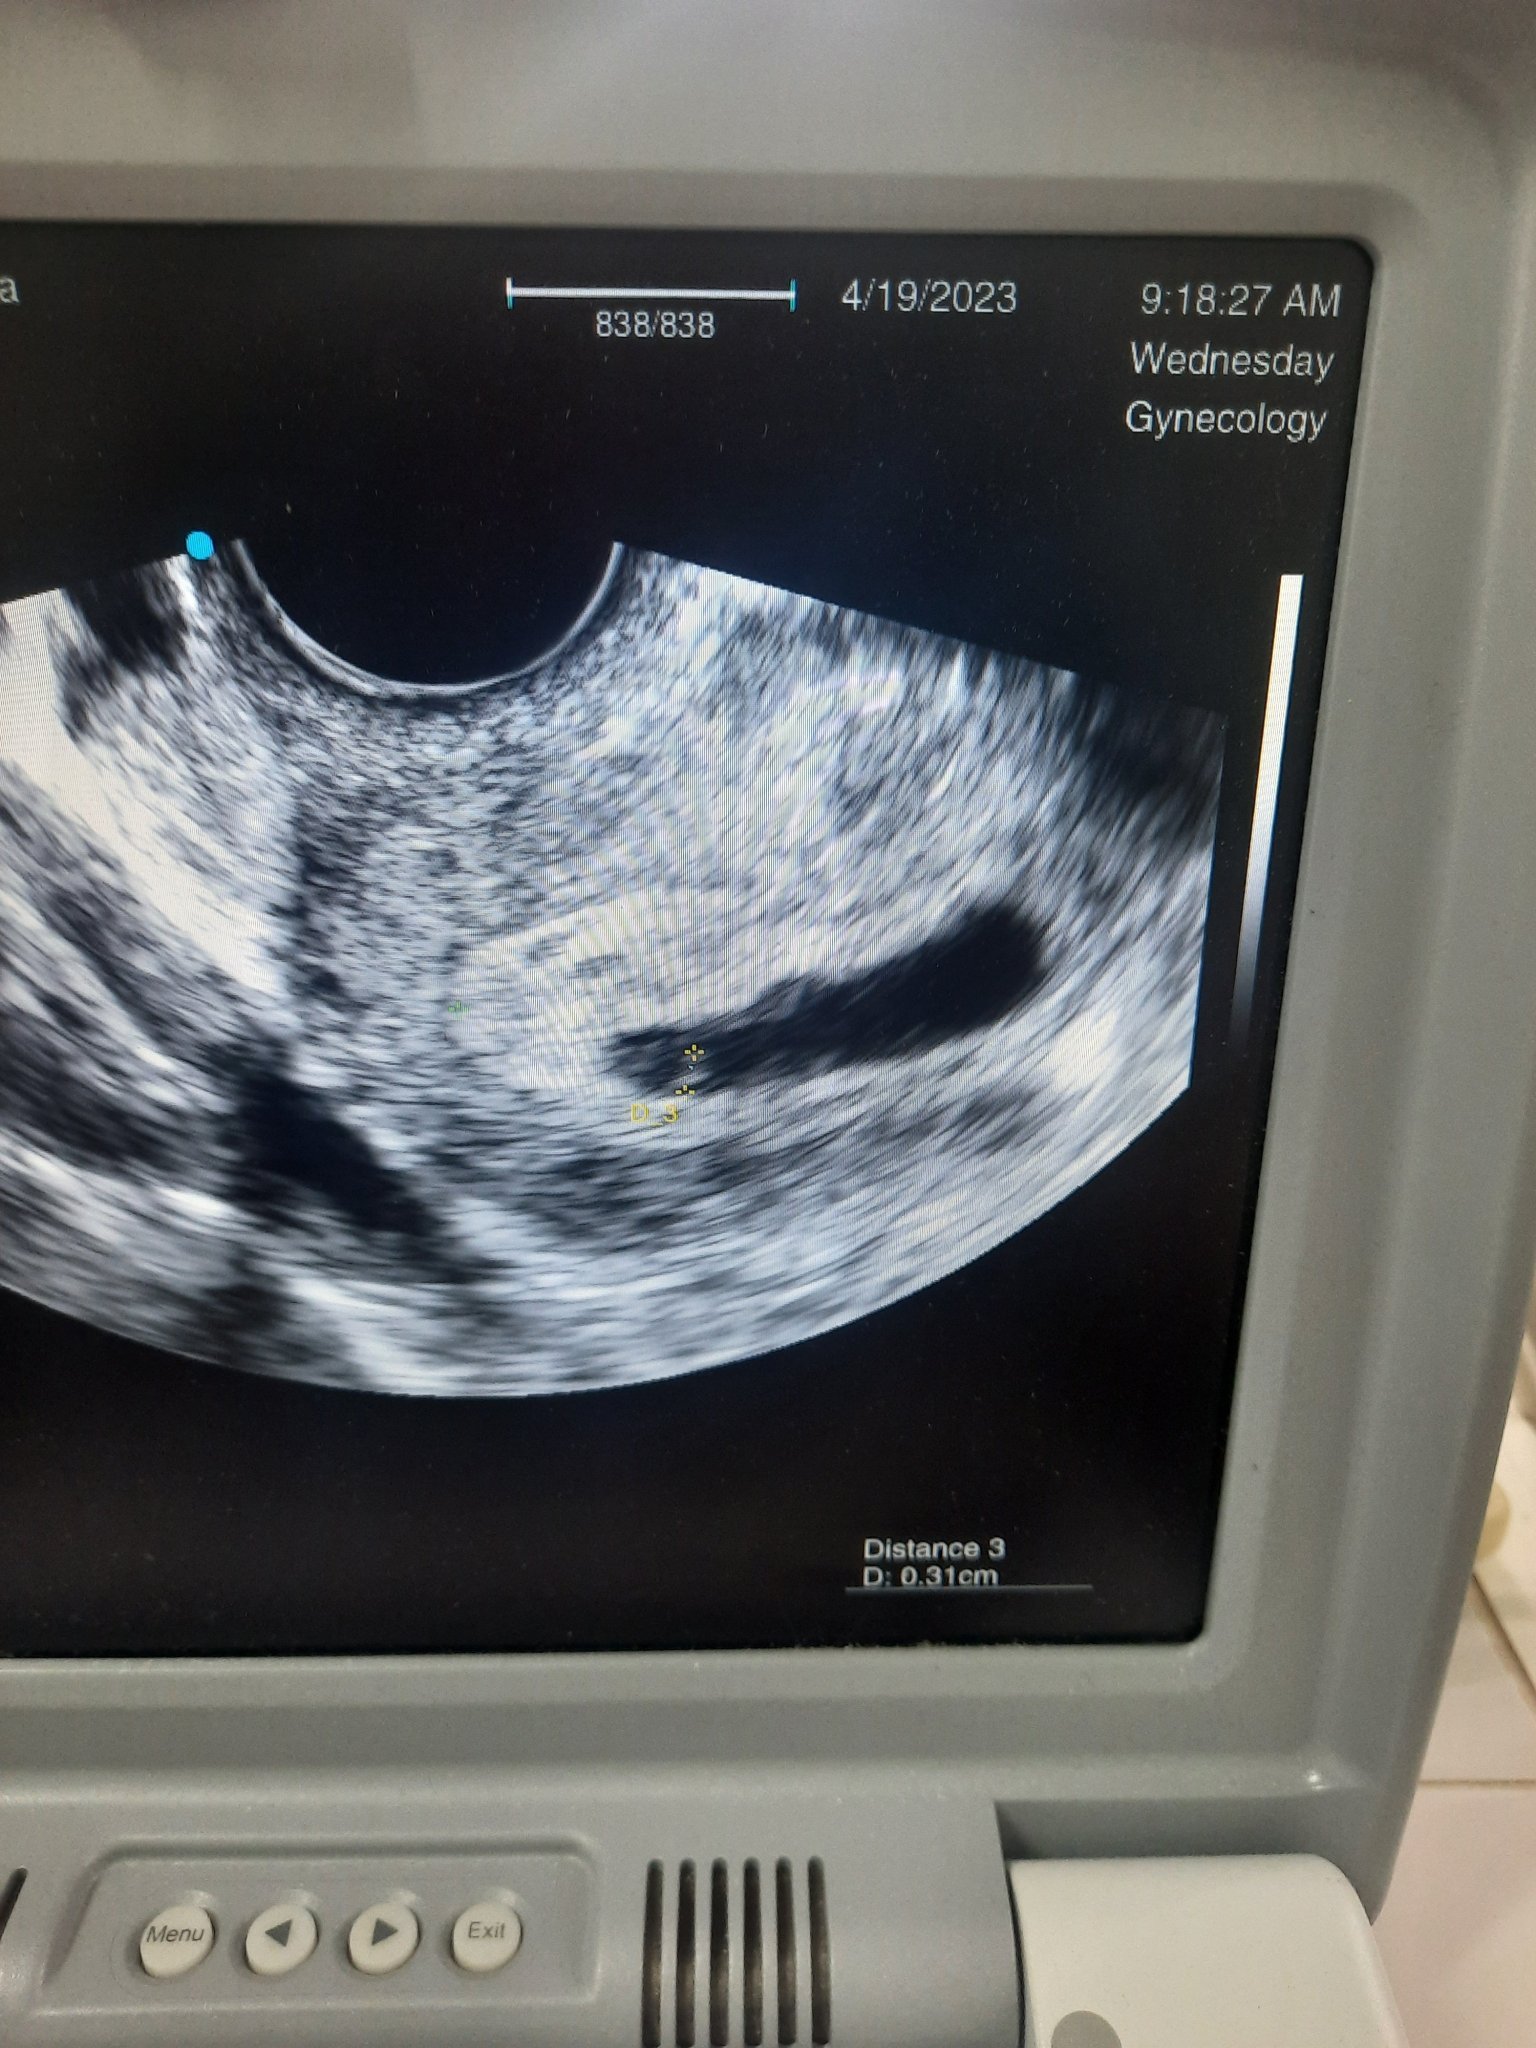

ПРМ на 21.02.2023г. На 30.03 бях на преглед и се видя плоден сак. Ходя при двама лекари (на частно и по здравна каса).  Бях на преглед на частно за установяване на ембрион и сърдечна дейност (по ПРМ съм в 8г.с),но на прегледа се установи че няма ембрион и сърдечен пулс и доктора има съмнение за кухо яйце,вика ме след седмица отново на преглед.

На следващия ден ходих на преглед при доктор със здравна каса,който видя ембрион и се изказа,че за сега нещата вървяли добре. И сега съм в пълен шок. Не знам какво да мисля. Прилагам снимки

Първата снимка е от първия преглед а втората е от прегледа на следващия ден.

На втората снимка се вижда, че има нещо в сакчето. Дори и да не отговаря на г.с. по ПМЦ, възможно е и да си имала по-късна овулация. Важното е да е там и да расте. При следващия преглед ще покаже. Пожелавам ти всичко да е наред!!!